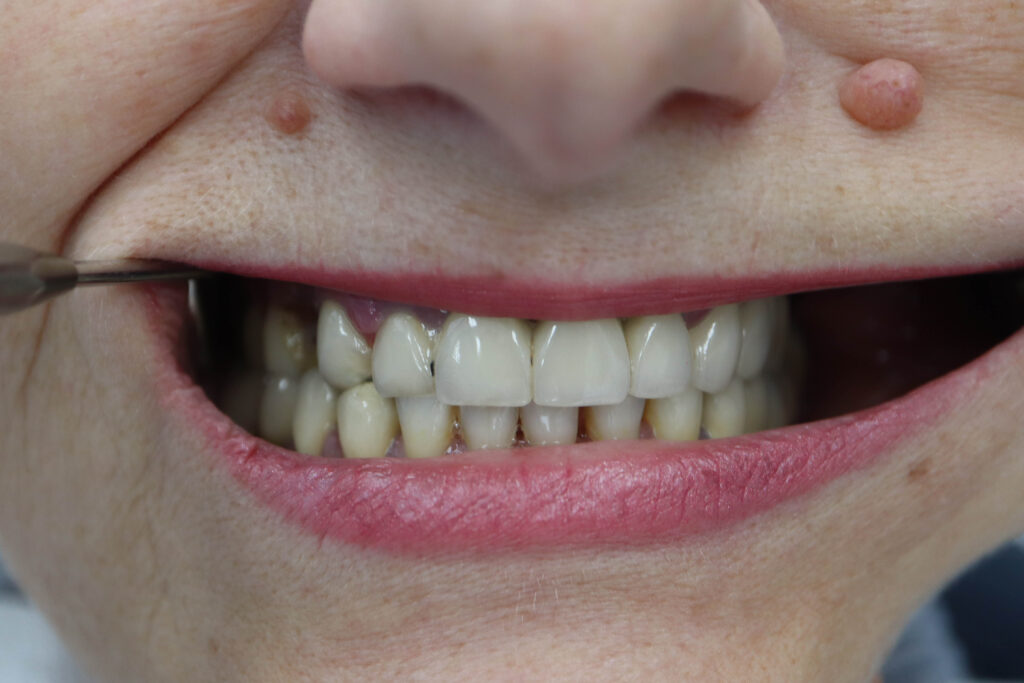

Ситуация до лечения

Пациент обратился с жалобами на эстетические недостатки. Диагноз: частичная вторичная адентия на верхней челюсти.

Зубы на верхней челюсти в неудовлетворительном состоянии.